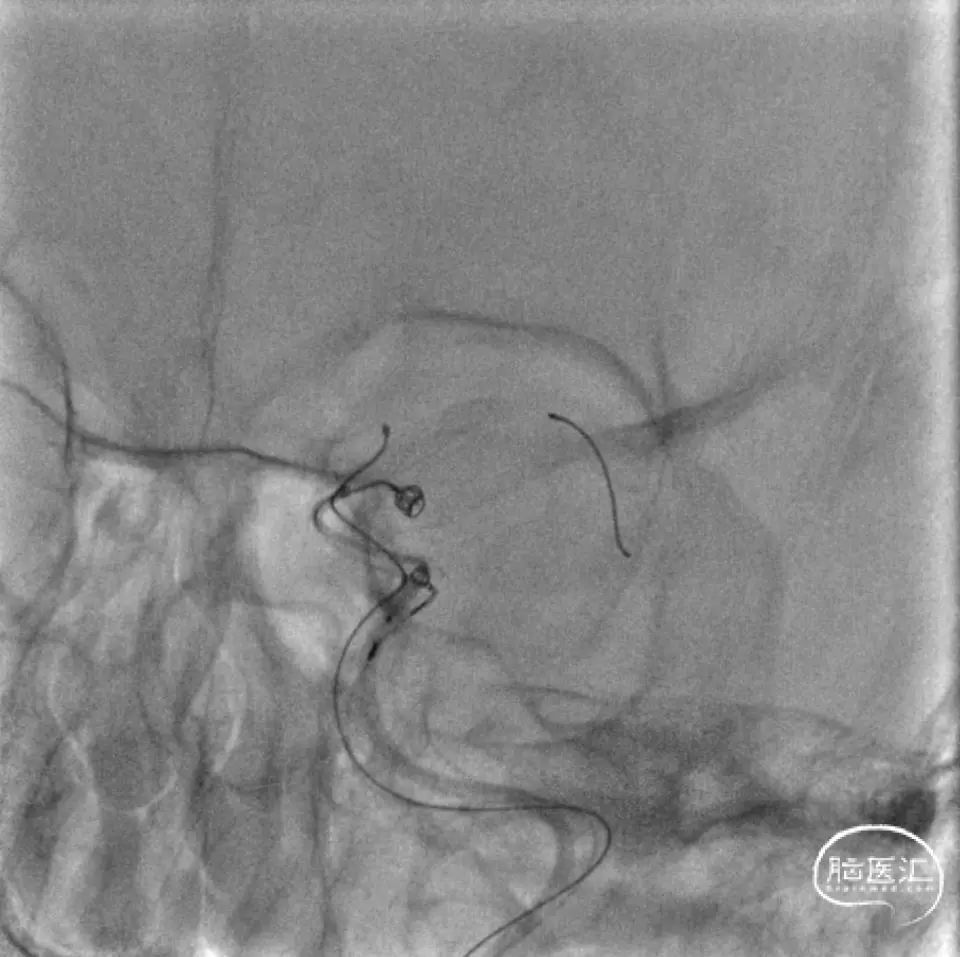

Synchro-2 导引Marksman超选大脑中动脉下干。45°预塑形Echelon-10超选进入下方动脉瘤(符合血流动力的责任动脉瘤),动脉瘤为相对宽颈,2mm*4cm弹簧圈难以稳定,更换3mm*4cm弹簧圈,成篮稳定,但难以完全盘入瘤腔。另一根Echelon-10头端塑“S”形,在Synchro-2导引下超选入上方动脉瘤,保留微导丝增加导管稳定性。半释放PED。

半释放PED,将3mm*4cm弹簧圈完全盘入下方动脉瘤,后将2mm*4cm收尾圈盘入,见致密栓塞,瘤颈封闭满意。后经另一根微导管,将两枚3mm*8cm成篮圈、一枚3mm*6cm成篮圈、两枚2mm*4cm Avenir系列收尾圈,盘入上方动脉瘤,可见瘤颈封闭满意、形成锚定。撤出微导管,微导丝按摩PED。

观察PED贴壁及打开满意。

正侧位及旋转造影见动脉瘤栓塞满意。